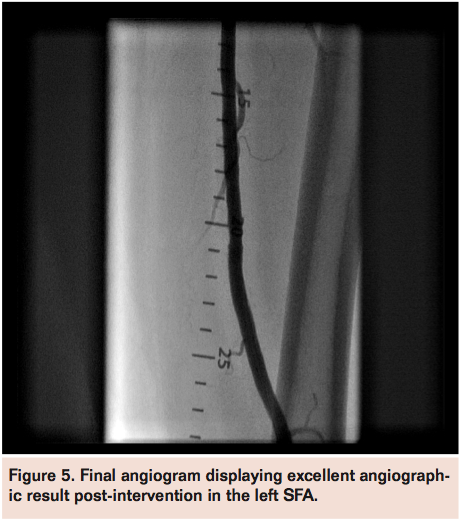

The proximal cap of the CTO was directly engaged using a Wildcat catheter (Avinger) (Figure 3), but manual rotation of the catheter tip met stiff resistance mid-lesion. The Juicebox motorized console (Avinger) was then attached to the Wildcat catheter, and with a constant tip rotation of 100 rpm, the remainder of the CTO was crossed. A distal popliteal angiogram through the Wildcat catheter central lumen confirmed intraluminal position (Figure 4). A 5 mm x 100 mm Angiosculpt scoring balloon (AngioScore, Inc.) was utilized to predilate the

occluded segment and 2 overlapping Supera 5 mm x 120 mm self-expanding stents (IDEV Technologies) were deployed in the left SFA. The final angiogram revealed brisk flow with 3-vessel runoff into the left foot (Figure 5). The patient tolerated the procedure well without complications and was discharged home the following day after observation post-intervention.